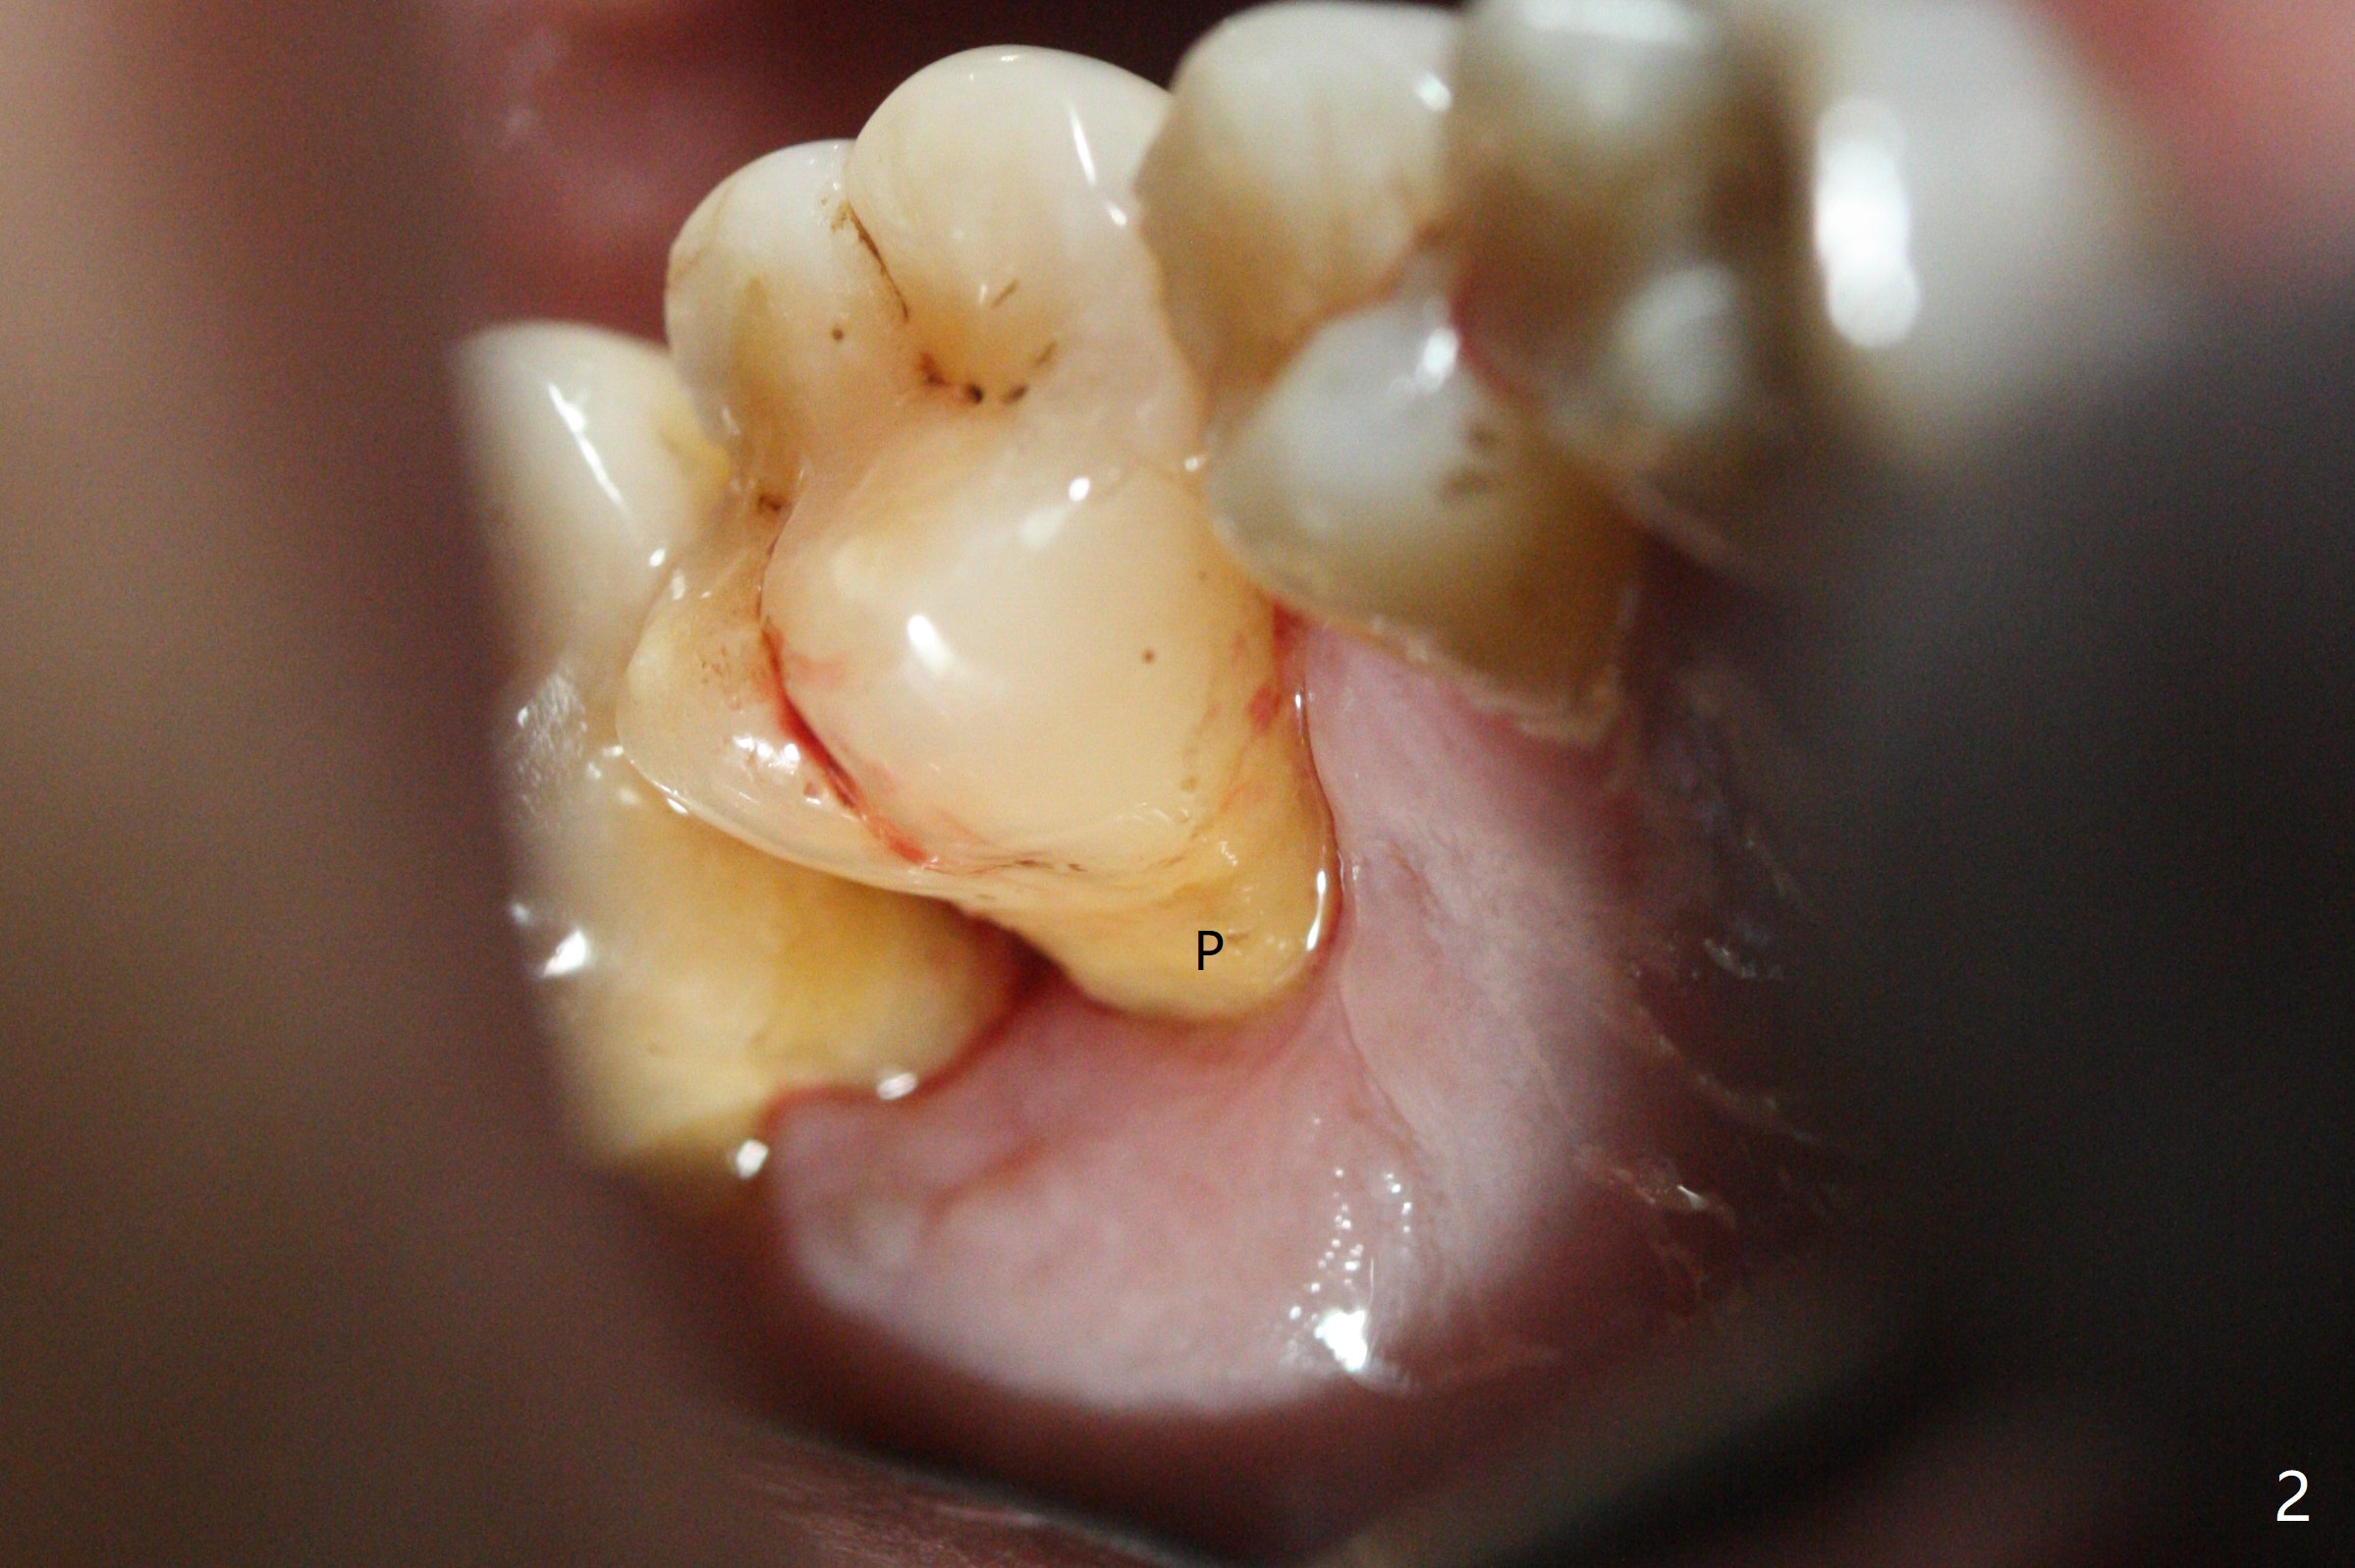

53岁男吸烟,牙周炎,咬合力大,3号牙颊侧(图一),腭侧(图二:P)牙龈退缩,尤其是近中颊侧根(图一:MB),拔牙后,中隔冠方(表面)有好像健康的牙龈(图三:*),近中,远中连接处切开(图三:虚线),将中隔牙龈推向近中颊侧牙槽窝(图四:箭头),修复退缩牙龈,而且暴露下面中隔(S),接着在它上面导板钻洞,避免软组织创伤。利用报废植体试图内提升(图五(红虚线:窦底)),最终正式植体完成提升(图六:黑*),初步在牙槽窝深部放置粘性骨粉(白*)后,放入基台,之后再次在植体,基台周围放置骨粉(图七:*),最后借助临时牙冠(图八,九:T)和外衬里(图八:R)封闭牙槽窝开口,G是近中颊侧迁移的牙龈。植体垂直进入上颌窦可以减少窦膜破裂(图五,六,九),术后没有鼻出血。术后1个月临时牙冠松动,去除牙冠和基台,安置愈合帽(图十)。表面骨粉遗失,但是颊侧移位的中隔牙龈好像帮助软组织预后。